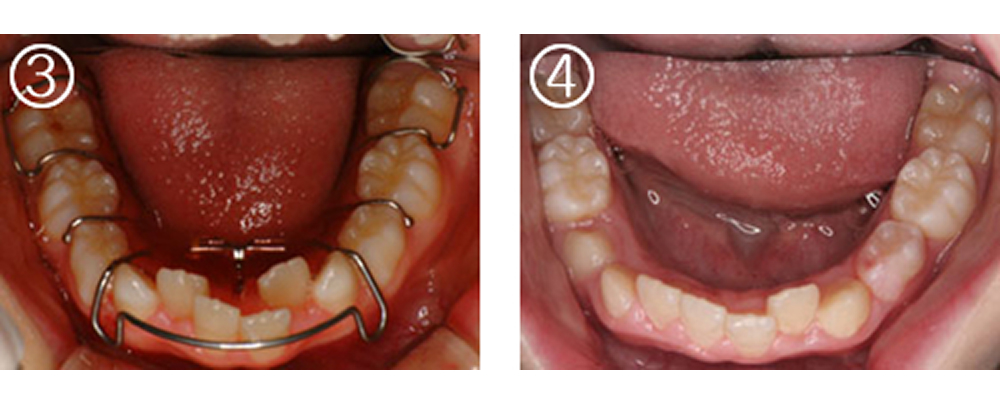

③装着した所

④1年後スペースが確保され、歯列弓全体も拡大されている。ここまで広がれば,非抜歯で矯正できます